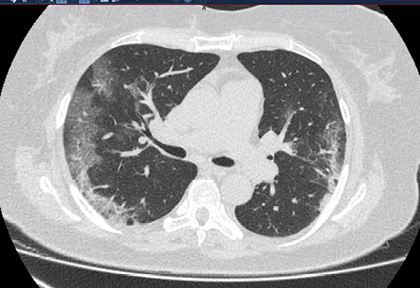

Routine clinical laboratory assays were performed in the hospital’s clinical laboratories. Clinical and laboratory information was extracted from the patients’ medical records. C reactive protein (CRP) in plasma was measured by immunoturbidimetry (Beckman Coulter, Krefeld, Germany). Interleukin-6 (IL-6) levels in plasma were measured by electrochemiluminescence (Siemens Medical Solutions Diagnostics, Siemens Healthcare, Erlangen, Germany). CT scans were read by experienced radiologists who scored results by severity using the criteria shown in Figure 1.

Figure 1. Clinical assessment of pneumonia severity based on computed tomography (CT) scores.

Scoring method: Mild (CT-1)—no more than three ground-glass opacities of <3 cm maximum diameter. Moderate (CT-2)—more than three ground-glass opacities; less than 50% involvement by visual assessment. Medium-heavy (CT-3)—ground-glass opacities and pulmonary consolidation; 50-70% involvement by visual assessment. Severe (CT-4)—diffuse ground-glass opacities with or without consolidation; more than 75% involvement by visual assessment.